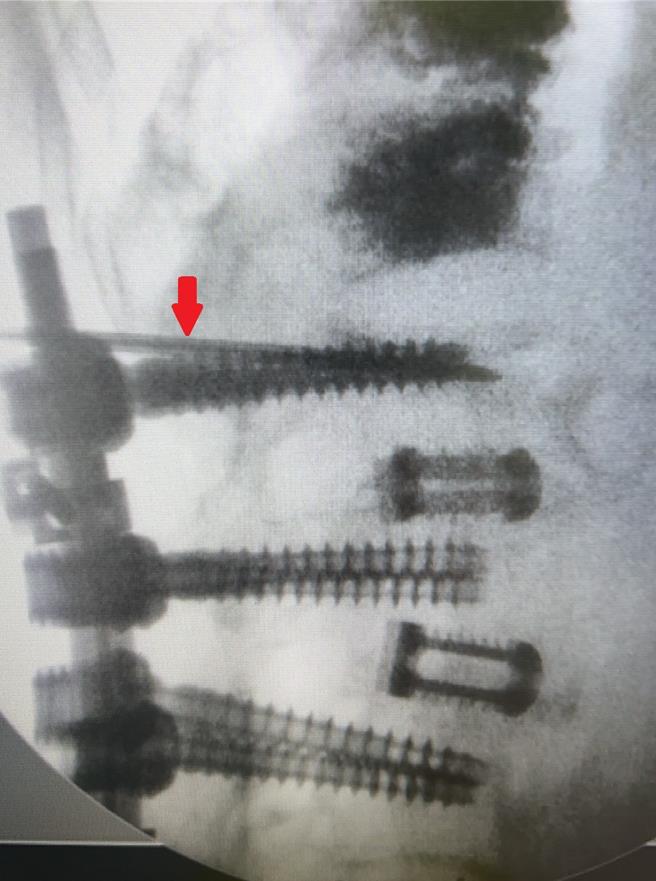

容志雄分享近日治疗的两个案例,一是高龄93岁的奶奶,过去脊椎第3、4、5节曾手术打钢钉,此次受伤刚好是在第3节上缘,评估病人因个子较高,加上第一支钢钉打入的位置较往下一些,因此利用上缘狭小的空间,顺利完成灌骨泥治疗。第二位病人是82岁的奶奶,个子娇小且钢钉位置打得很好,能打入骨泥的空间更小,所幸在使用孩童专用的细小钢针后,也成功灌入骨泥,解决压迫性骨折的疼痛。两位病人的困难度都相当高,所幸在手术过程中透过C型臂X光机准确的定位,及医师专业的判断,才能在非常狭窄的空间下,精准地将骨泥灌入受伤位置。